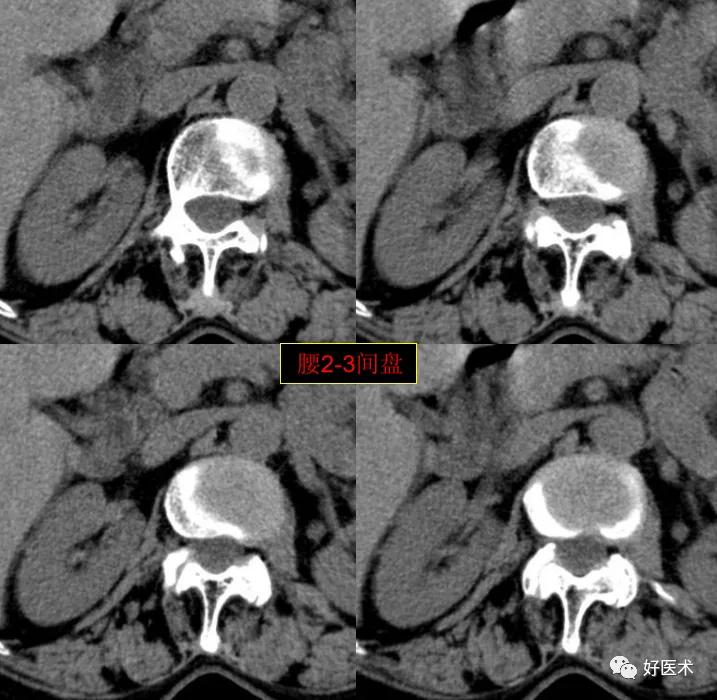

CT图像,腰椎常规采用序列扫描,腰椎体2层,腰间盘4层,层厚2.5mm,一般扫描范围包括腰2--骶1椎体及所属间盘。

腰2-3间盘未见著变。